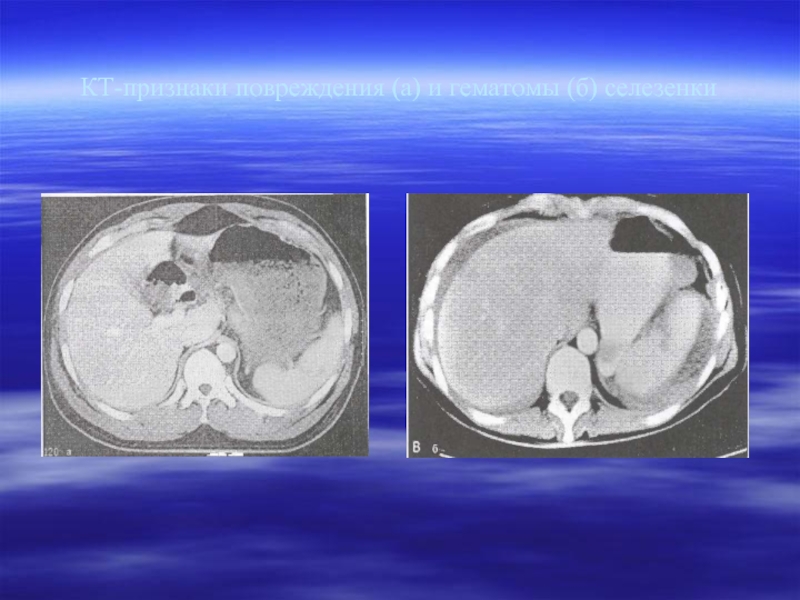

Слайд 29КТ-признаки повреждения (а) и гематомы (б) селезенки